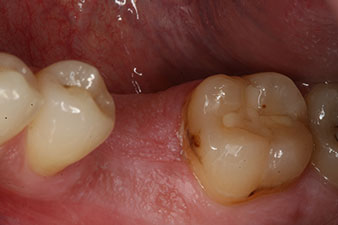

Fig. 6: Ten weeks later the gingiva former, which was screwed in place after placement of the implant, can be removed. In the linguo-buccal direction the ISQ value was virtually unchanged at 63 (measuring probe in proximity at a distance of 2-3 mm).

The implant was uncovered two months later and a gingiva former was screwed in (no picture).

After healing of the soft tissue, the implant stability was measured again before delivery of the prosthetic restoration.

Both values were virtually unchanged and were between the medium and the high range – where the lower value is always used as the reference value that determines the treatment.

impression

Fig. 8: The impression for the final crown is taken.

Therefore, successful osseointegration and adequate biological stability could be recorded, which enabled an impression to be taken in the same session.